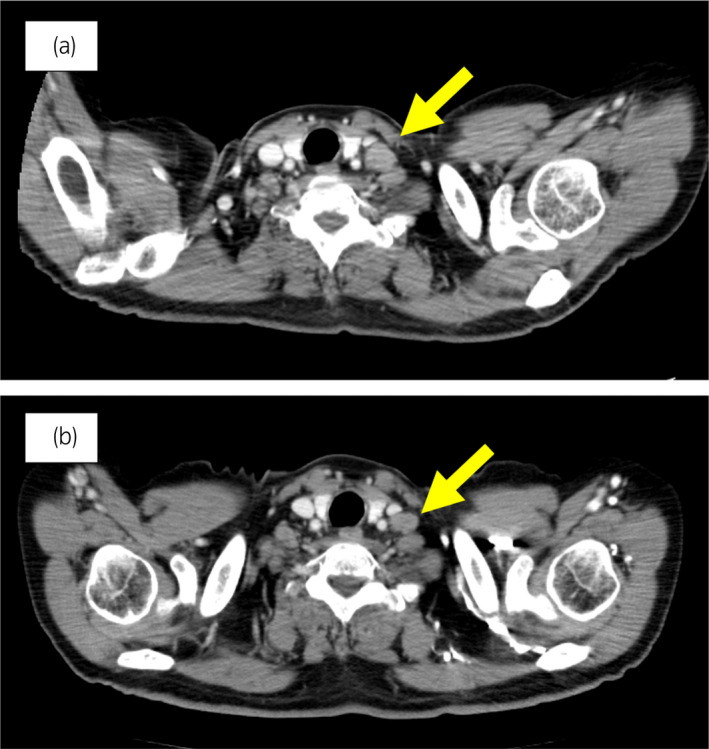

一名 78 歲男性被診斷為 cT3bN0M0,GS 為 4 + 4 =⟩8,PSA 水平為 15.2 ng/ml 7 年前,并接受了前列腺切除術。 六個月后,PSA 升高并開始雄激素剝奪治療。 兩年后,開始使用比卡魯胺治療 CRPC。 服用比卡魯胺五個月后,患者被轉診至佳學基因檢測合作醫(yī)院。 在接下來的 2 年內,依次給予恩雜魯胺、多西他賽和卡巴他賽。 多西他賽前的 MRI 顯示髂骨轉移,多西他賽和卡巴他賽治療后消失。 開始使用卡巴他賽后 6 個月,他出現(xiàn)雙側盆腔淋巴結腫大,并在膀胱后壁發(fā)現(xiàn)轉移性腫瘤。 在進行經尿道切除術 (TUR) 期間,從膀胱中的轉移性腫瘤獲得組織樣本。 病理檢查顯示嗜鉻粒蛋白 A 陽性,NSE 水平升高,因此我們診斷為 NEPC。 卡鉑和依托泊苷聯(lián)合治療縮小了腫瘤。 此后,在 24 個月內進行了 17 個療程,疾病得到控制。 由于神經病變和疲勞而停止化療。 隨后,患者出現(xiàn)盆腔淋巴結轉移進展(圖 4a)。 通過血液檢測 (BRCAnalysis®?) 進行的基因檢測對 BRCA 突變呈陰性。 使用 TUR 時收集的膀胱轉移組織進行腫瘤正確用藥850基因檢測。 結果顯示,該患者的體細胞 BRCA2 突變呈陽性。 在奧拉帕尼給藥后的 3 個月內,淋巴結從 21.0mm 縮小到 7.5mm(圖 4b)。 PSA 從 1.42 下降到 0.07 ng/ml,NSE 從 22.3 下降到 11.8 ng/ml。

圖 4:病例 2:奧拉帕尼治療前和治療后 3 個月的盆腔淋巴結 CT 圖像。 (a) 治療前和 (b) 奧拉帕尼治療后 3 個月。 黃色箭頭顯示轉移淋巴結。